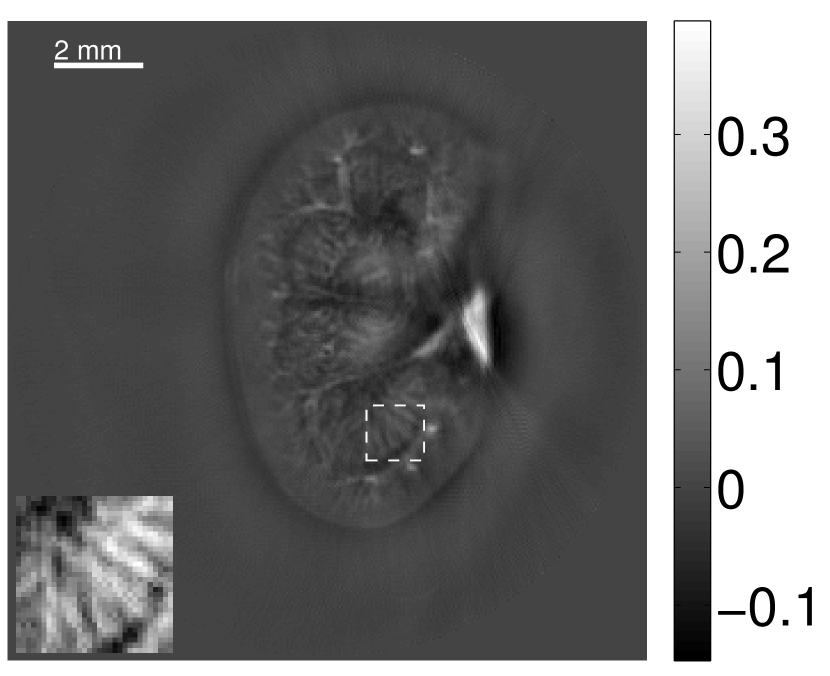

The images and EIRs reconstructed by use of the VP algorithm that was based on the 2D imaging model that neglected the SIR are shown in Figures 15 and 16. The latter figure contains results corresponding to different values for the regularization parameter . From Fig. 15, it can be observed that use of the conventional iterative method that utilized the measured EIR resulted in distortions and loss of details in the reconstructed images. Use of the VP algorithm improved the contrast and the details in the reconstructed images (Fig. 15(c) and 16(a)). Furthermore, the images reconstructed by use of the VP algorithm had a more uniform background.

In Figure 17, the results corresponding to use of the 3D imaging model that incorporated SIR effects are shown. The EIR estimated by the VP algorithm is also shown. In Figure 18, images and EIRs reconstructed by use of the VP algorithm with different regularization parameters values are shown.

Similar to the case described above where the transducer SIR was neglected, these results reveal that use of the VP algorithm can produce images with a cleaner background and enhanced spatial resolution than yielded by use of a conventional iterative algorithm that employed the measured EIR. For example, detailed information regarding the vessels near the organ’s periphery was better preserved by the VP algorithm than by the conventional iterative algorithm. These images corroborate our assertion that the VP algorithm can significantly reduce the artifacts and distortions in the reconstructed image. It is also worth pointing out that, unlike the numerical phantom studies, the artifacts and distortions in the images may be caused not only by the inaccurate EIR but also by other factors, such as neglecting acoustic heterogeneities and the variation of the EIRs among the elements of the transducer array. In such cases, the EIR estimated by the VP algorithm represents an effective system impulse response that minimizes the inconsistency between the measured data and the imaging model.